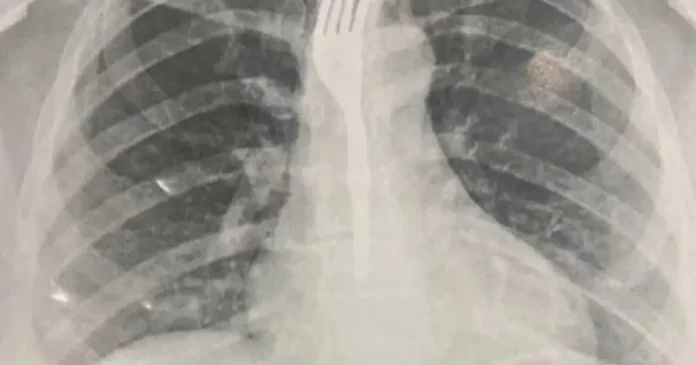

Segundo informações do portal Achei Sudoeste, a paciente — que não teve o nome divulgado — foi levada inicialmente ao Hospital Geral de Guanambi (HGG), onde exames de imagem mostraram que o utensílio estava alojado no esôfago em posição de risco.